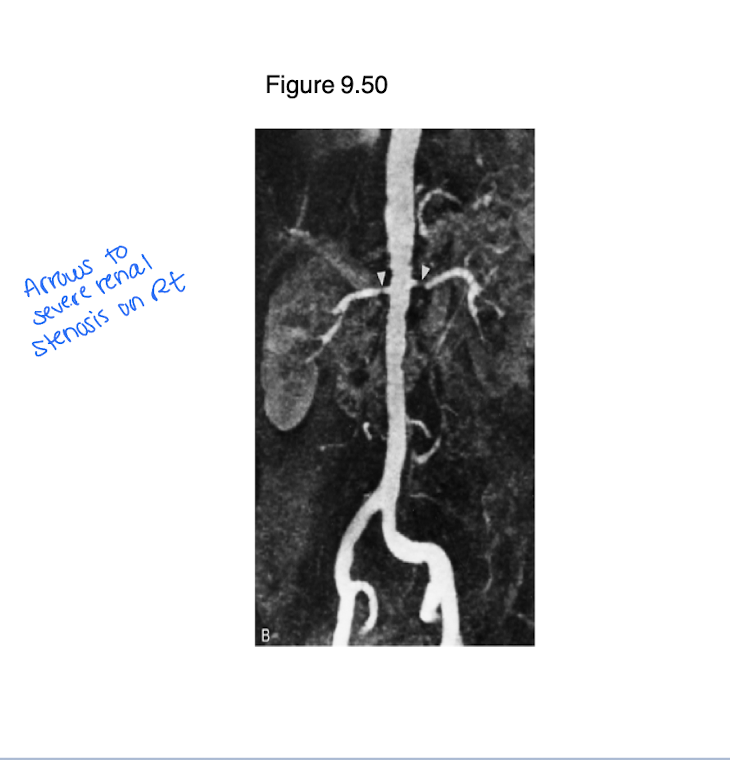

Vascular lesions can lead to renal artery occlusion. What diagnostic tool would be used to evaluate?

Doppler u/s

Angiography